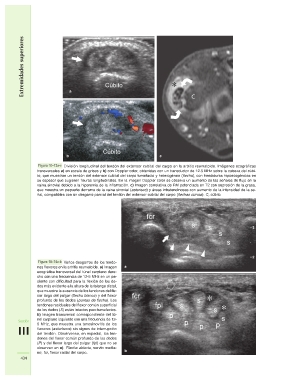

Figura 10–73a-c División longitudinal del tendón del extensor cubital del carpo en la artritis reumatoide. Imágenes ecográficas

transversales a) en escala de grises y b) con Doppler color, obtenidas con un transductor de 12-5 MHz sobre la cabeza del cúbi-

to, que muestran un tendón del extensor cubital del carpo tumefacto y heterogéneo (flecha), con hendiduras hipoecogénicas en

su espesor que sugieren fisuras longitudinales. En la imagen Doppler color se observa un aumento de las señales de flujo en la

vaina sinovial debido a la hiperemia de la inflamación. c) Imagen correlativa de RM potenciada en T2 con supresión de la grasa,

que muestra un pequeño derrame de la vaina sinovial (asterisco) y áreas intratendinosas con aumento de la intensidad de la se-

ñal, compatibles con un desgarro parcial del tendón del extensor cubital del carpo (flechas curvas). C, cúbito

Sección Figura 10–74a-b Varios desgarros de los tendo- a fpl s s

nes flexores en la artritis reumatoide. a) Imagen

III ecográfica transversal del túnel carpiano dere- fcr p s

cho con una frecuencia de 12-5 MHz en un pa- p

434 ciente con dificultad para la flexión de los de- b s

dos más evidente a la altura de la falange distal, pp

que muestra la ausencia de los tendones del fle-

xor largo del pulgar (flecha blanca) y del flexor

profundo de los dedos (puntas de flecha). Los

tendones residuales del flexor común superficial

de los dedos (S) están intactos pero tumefactos.

b) Imagen transversal correspondiente del tú-

nel carpiano izquierdo con una frecuencia de 12-

5 MHz, que muestra una tenosinovitis de los

flexores (asteriscos) sin signos de interrupción

del tendón. Obsérvense, en especial, los ten-

dones del flexor común profundo de los dedos

(P) y del flexor largo del pulgar (fpl) que no se

observan en a). Flecha abierta, nervio media-

no; fcr, flexor radial del carpo.